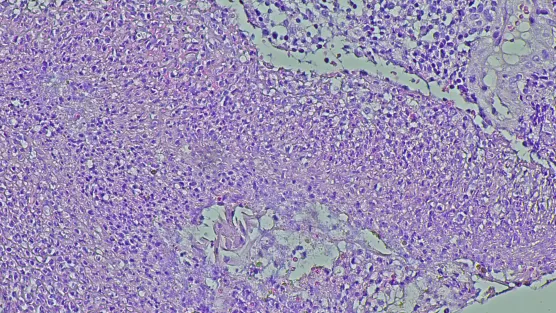

Ciężkie skutki choroby alkoholowej

Choroba alkoholowa może powodować m.in. marskość wątroby, ostre zapalenie trzustki, uszkodzenia mózgu. Zmiany można zatrzymać, ale są w zasadzie nieodwracalne. Do szpitala trafia wiele młodych osób z ciężkimi uszkodzeniami, wynikającymi z picia alkoholu. Pomimo wysiłków lekarzy, nie udaje się ich często uratować – wyjaśnia prof. dr hab. n.med. Leszek Czupryniak, kierownik Kliniki Diabetologii i Chorób Wewnętrznych Warszawskiego Uniwersytetu Medycznego.